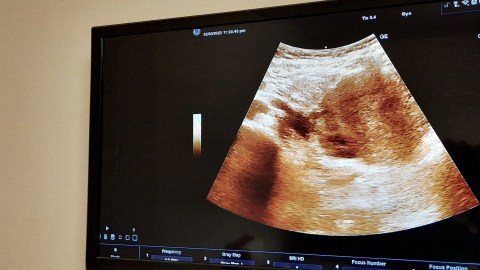

Ultrasonografía de una mujer embarazada. Crédito: Tamer A Soliman | Shutterstock